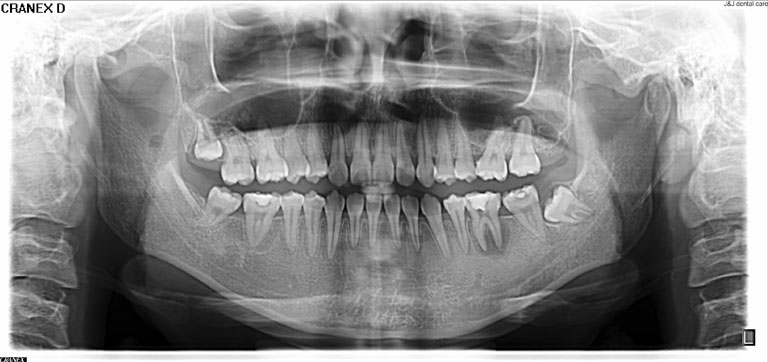

Root Canal Treatment Solution

Untuk setiap kondisi masalah gigi kamu, selalu ada solusi terbaik.

2.Informasi yang selalu kami sampaikan bahwa setiap gigi di dalam mulut adalah bagian yang tidak tergantikan. Merawat dan mempertahankan menjadi pilihan pertama yang perlu dipertimbangkan.

Penanganan yang tepat dengan alat dan teknologi yang memadai menjadikan hasil yang optimal

3. Gigi yang sehat adalah yang bisa berfungsi balk dan bertahan lama dalam mulut.